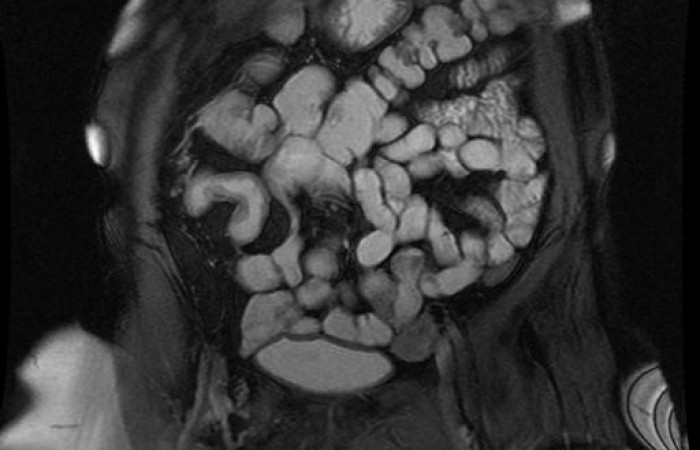

ˇ cholangiopankreatografia MR (MRCP) - badanie MR dróg żółciowych i trzustkowych bez podania środków kontrastowych

Diagnostyczne stacje komputerowe pozwalają na przekształcanie danych obrazowych oraz otrzymywanych w badaniach spektroskopowych i czynnościowych. Oprócz klasycznych przekrojów można otrzymać obrazy trójwymiarowe oraz w opcji wirtualnej endoskopii naczyń, dróg żółciowych i moczowych czy układu komorowego mózgu.